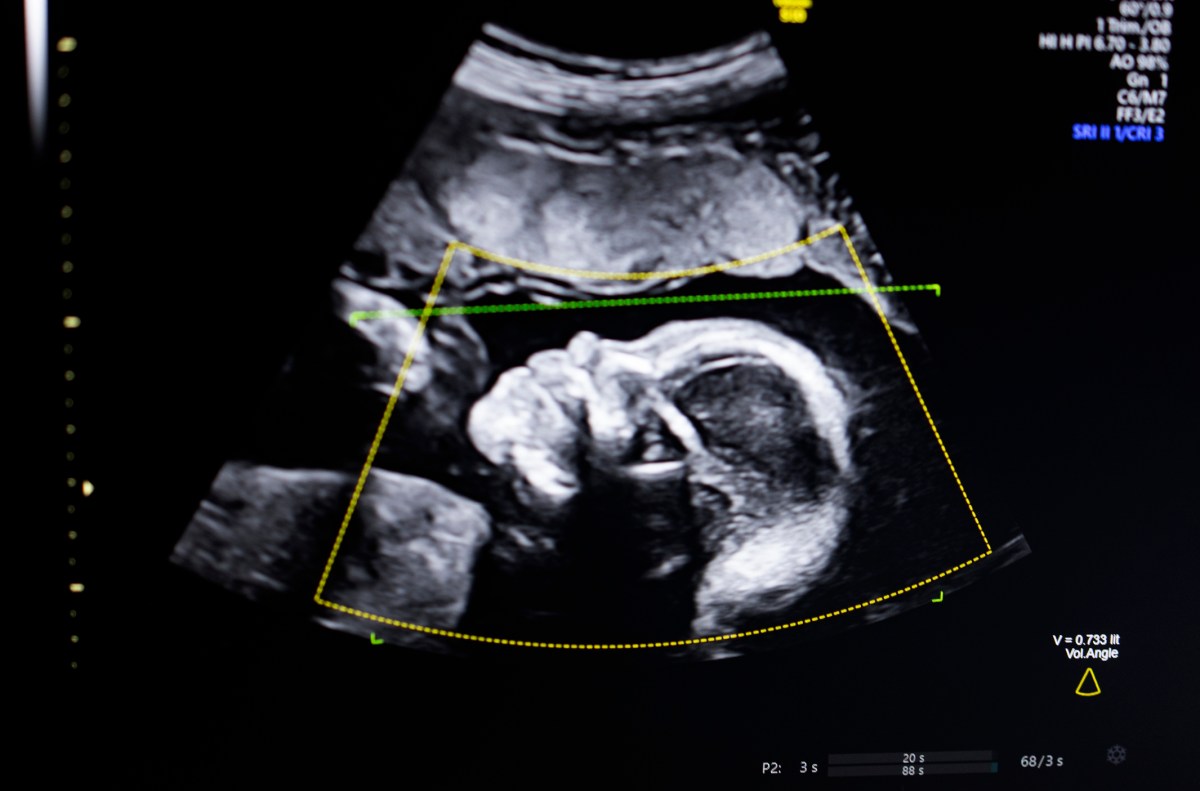

Bustami indicó que el ultrasonido prenatal se ha convertido en la piedra angular del monitoreo de embarazos, pero las imágenes de baja calidad pueden conducir a diagnósticos erróneos. La inteligencia artificial busca reducir estos errores al mejorar la calidad y consistencia de las evaluaciones ecográficas.